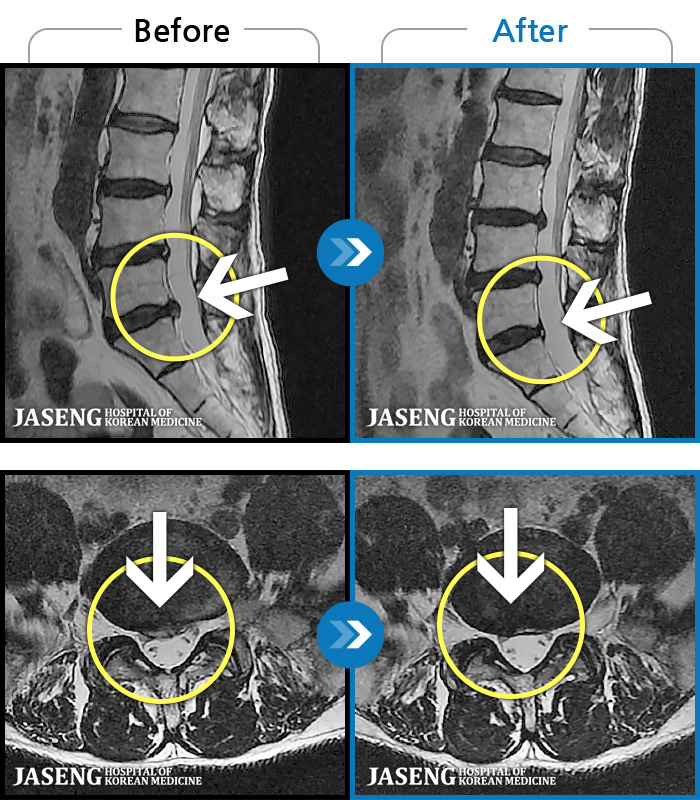

[] 03.04.01~09.11.01

ȯںп Ǹ ǿ ԿǾ, ο ġ ۿ Ƿ ġḦ Ͻñ ٶϴ.